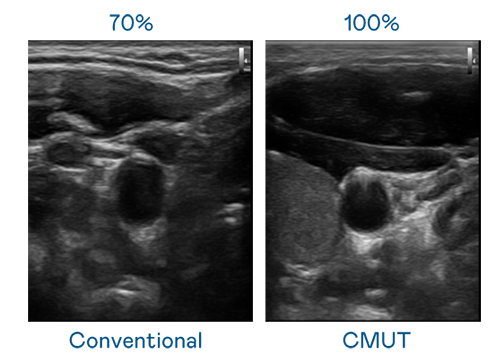

CMUT 技术是一种用电容式微机电元件来产生超音波讯号的技术。与传统 PZT 压电式技术相比,CMUT 频宽增加 30%,更宽频的超音波讯号让影像解析度大幅提升,是实现高影像品质医疗超音波扫描、促进精准医疗发展的关键技术。

超音波影像的解析度高低,首先取决于探头能发出的讯号频宽。PA视讯 CMUT 可提供高清晰的超音波讯号,提供高频宽、高灵敏度、影像纹理细节更高的超音波影像,协助医护人员缩短影像判读时间及利用精准的医疗影像进行诊断。